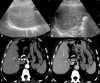

The Abernethy malformation consists of a congenital extrahepatic portosystemic shunt and is believed to be extremely rare in humans. The potential implications of abnormal portovenous shunting and decreased hepatic portal flow are numerous and potentially serious. Although congenital extrahepatic portosystemic shunts are increasingly suspected and diagnosed in specialized centres, much of their clinical presentation and natural history is not fully understood. Symptoms of portosystemic shunt are mainly caused by increased levels of ammonia, which lead to signs of encephalopathy. Therapeutic options depend on the type of shunt and its clinical course, so the classification of the congenital portosystemic shunt is a key finding in these patients.